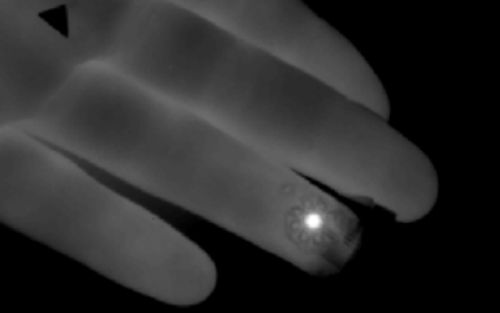

这一灵活的薄片,可贴敷于皮肤表面,借助热传感器准确测量血管的血流量,有望为医生提供实时、且高准确率的血检指标。

设备的工作原理:加热元件定位在皮肤表面的动脉或者静脉附近,通过加热装置加热皮肤,随后血管中血液带走热量,通过加热元件附件的温度传感器记录流失热量的方向和数值。研究人员通过将读出的数值与血液流动的流体动力学结合,则可以对血液流量定量。